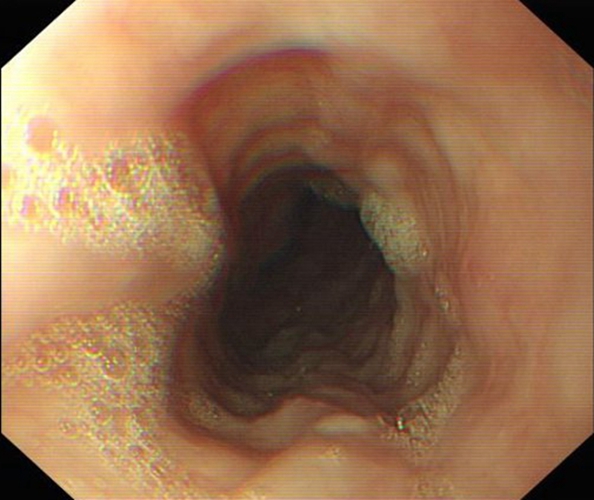

急性胃炎

急性胃炎胃部

急性胃炎相關文章